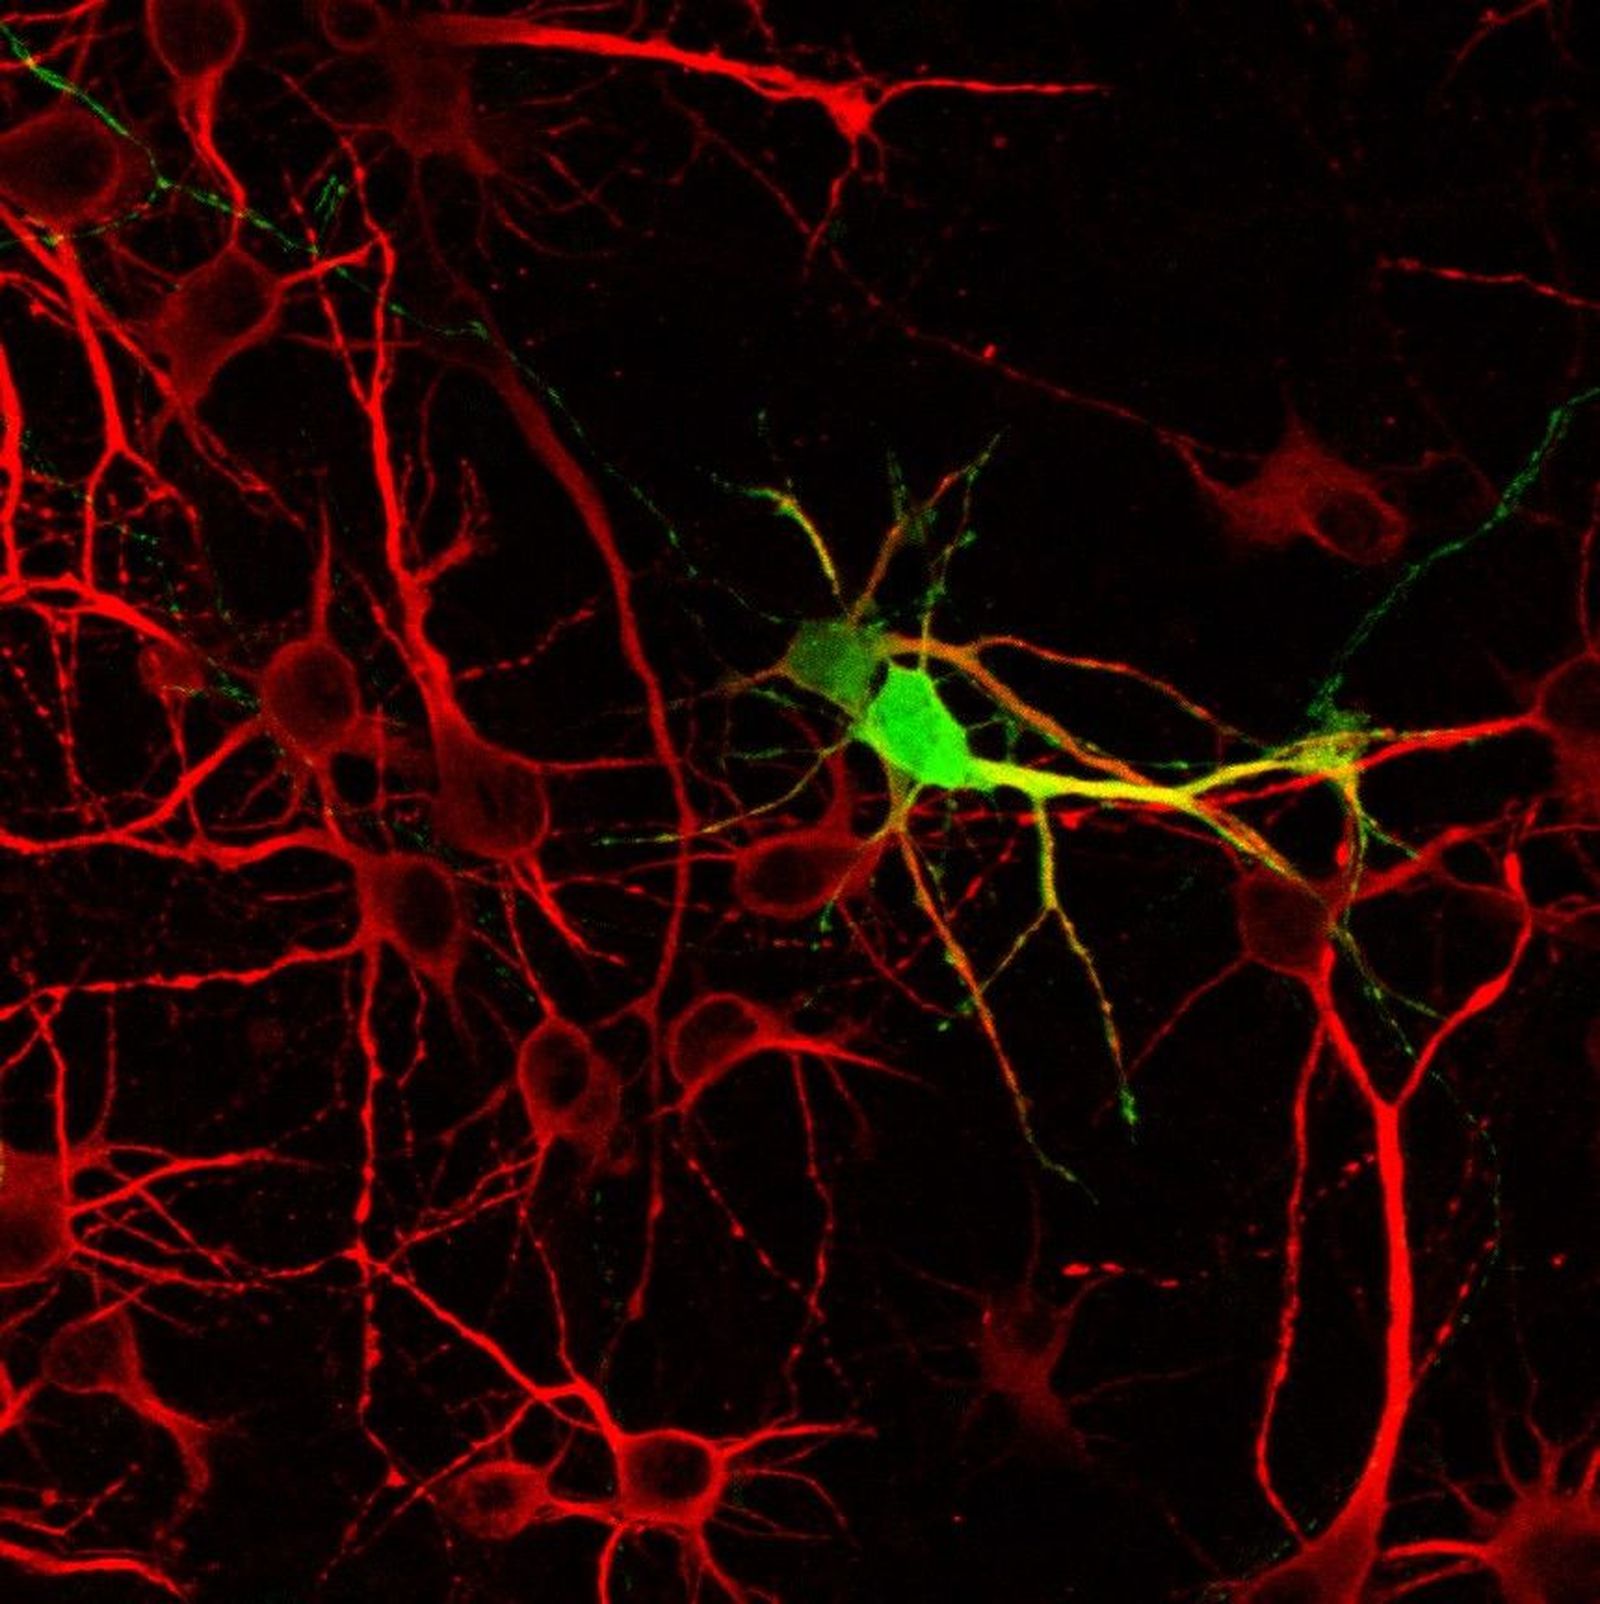

Neuronas en cultivo. Imagen: Neurobiología Molecular IBSAL

Este equipo trabaja tanto con cultivos de neuronas como con modelos animales experimentales en busca de los biomarcadores, moléculas que, en este caso, tienen una función relevante en la muerte neuronal. “El siguiente paso es ver si realmente esas moléculas tienen un impacto en la enfermedad en el humano. Si nosotros sabemos cuál va a ser la progresión de esas enfermedades con los biomarcadores, se pueden realizar medicinas, tratamientos personalizados, para que los pacientes tengan una mayor recuperación”, afirma la experta.